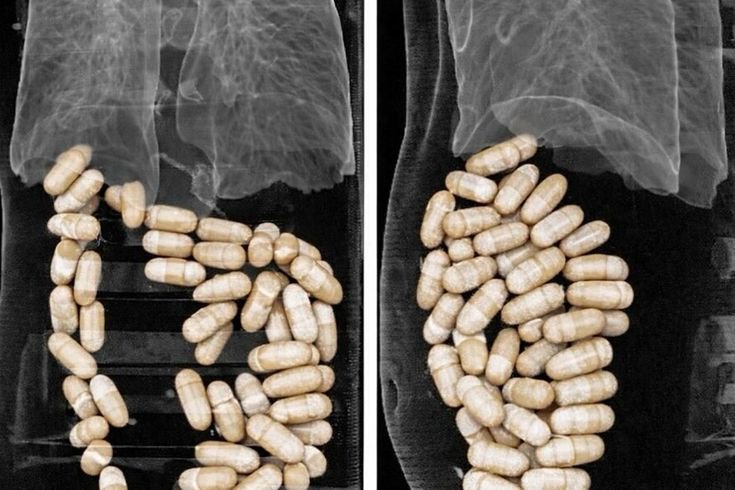

“diyarbakır'da su arıtma cihazında 1 kilo 50 gram esrar ele geçirildi” için görseller sonuçları